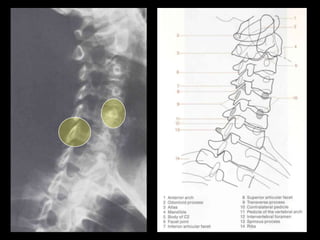

This document provides an overview of normal musculoskeletal imaging. It discusses basic x-ray concepts and densities. It then reviews normal anatomy as seen on x-rays of the skull, spine, pelvis, chest, and extremities. Key anatomical structures are labeled on example x-rays for the shoulder, hip, knee, and foot. Quizzes are included to test recognition of anatomical structures and patient age based on x-rays.